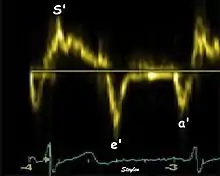

The method measures annular velocities to and from the probe during the heart cycle.

Annular velocities summarize the longitudinal contraction of the ventricle during systole, and elongation during diastole. Peak velocities are commonly used.

Systolic function

Peak systolic annular velocity (S') of the left ventricle is as close to a contractility measure as you can get by imaging[4] (bearing in mind that any imaging method only measures the result of fibre shortening, without measuring myocyte tension). S' has become a reliable measure of global function[5][6][7][8] It shares the advantage of annular displacement, that it is reduced also in hypertrophic hearts with small ventricles and normal ejection fraction (HFNEF), which is often seen in Hypertensive heart disease, Hypertrophic cardiomyopathy and Aortic stenosis.[9]

Diastolic function

As the ventricle relaxes, the annulus moves towards the base of the heart, signifying the volume expansion of the ventricle. The peak mitral annular velocity during early filling, e' is a measure of left ventricular diastolic function, and has been shown to be relatively independent of left ventricular filling pressure.[12][13][14] If there is impaired relaxation (Diastolic dysfunction), the e' velocity decreases. After the early relaxation, the ventricular myocardium is passive, the late velocity peak a' is a function of atrial contraction. The ratio between e' and a' is also a measure of diastolic function, in addition to the absolute values.